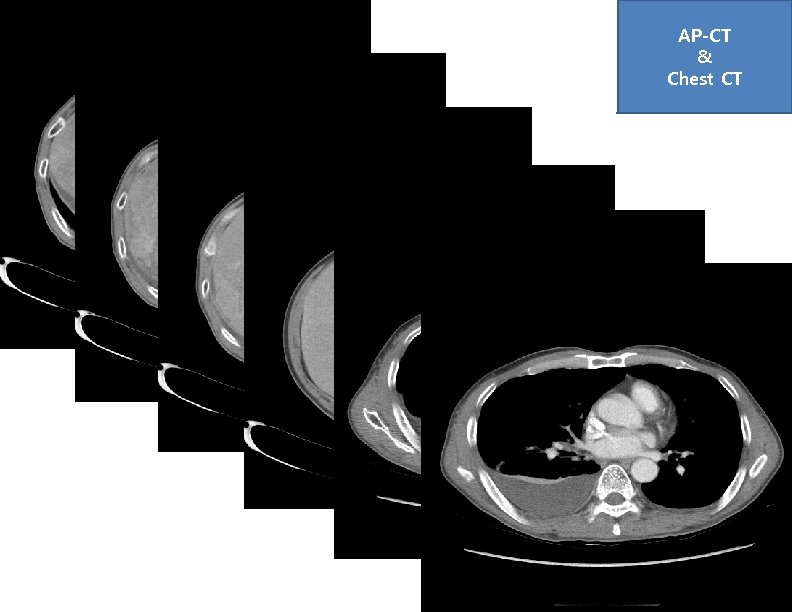

AP-CT & Chest CT AP-CT & Chest CT